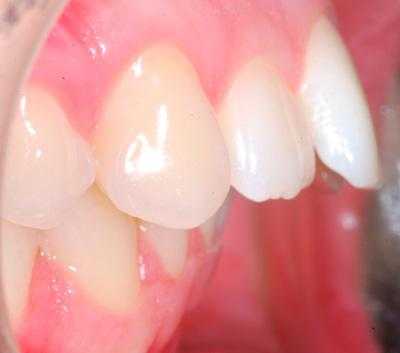

Внутриротовые признаки

В полости рта дистальный прикус определяется по выступающим вперед верхним фронтальным зубам. В норме, при ортогнатическом прикусе, верхние резцы перекрывают нижние примерно на 1/3. При дистальной патологии между верхними и нижними резцами образуется расстояние — «саггитальная щель».

Неправильное смыкание зубов всегда означает неравномерное распределение нагрузки на разные зубы — пока отдельные зубы в жевательном процессе не участвуют, другим приходится перерабатывать большей объем пищи с большей интенсивностью. Это предсказуемо приводит зубы к более быстрому изнашиванию. Под риском преждевременного поражения оказывается вся зубо-челюстная система в целом:

- ткани пародонта. Образуются рецессии десны, десневые карманы, воспаления.

- зубная эмаль. Под давлением в придесневой области на эмали возникают сколы —клиновидные дефекты. При неправильном смыкании зубы стираются.